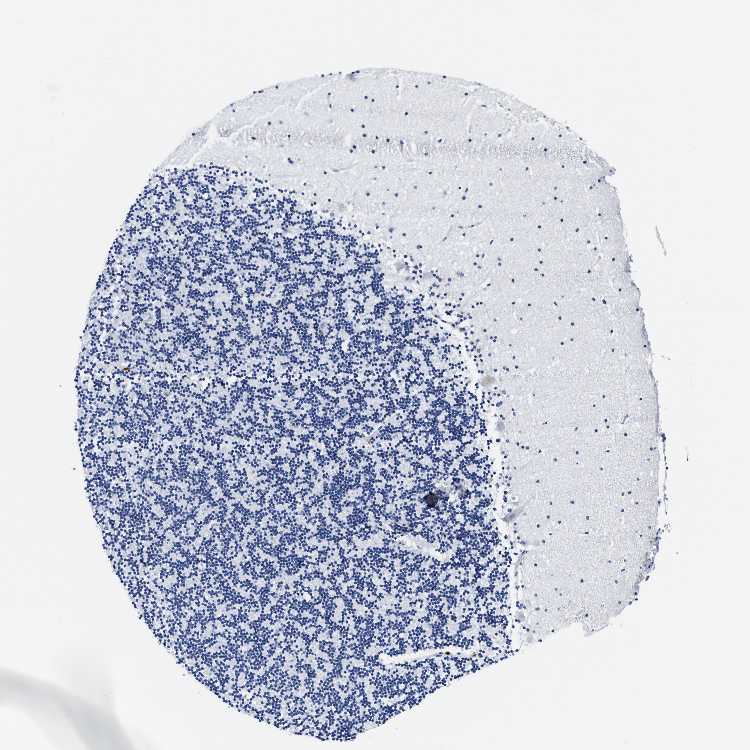

CEREBELLUM - Antibody stainingi

Antibody staining in the annotated cell types in the current human tissue is reported as not detected, low, medium, or high, based on conventional immunohistochemistry profiling in selected tissues. This score is based on the combination of the staining intensity and fraction of stained cells.

Each image is clickable and will lead to virtual microscopy that enables deeper exploration of all samples and also displays staining intensity scores, fraction scores and subcellular localization as well as patient and tissue information for each sample.

Antibody HPA016810Antibody HPA023964

Purkinje cells Not detectedMedium

Cells in granular layer Not detectedLow

Cells in molecular layer Not detectedLow